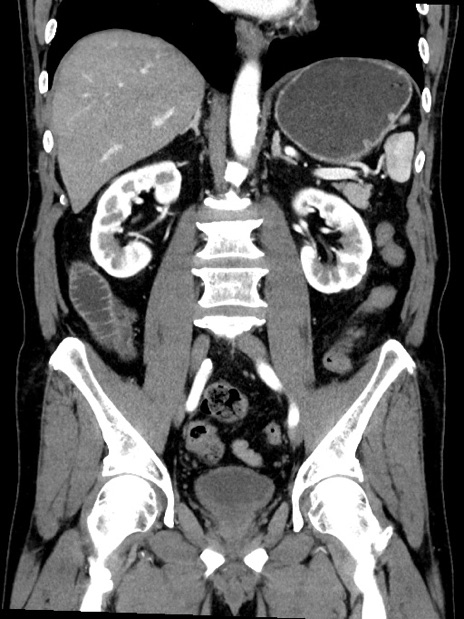

症例35(冠状断像)

【症例】70歳代 男性

【主訴】腹部膨満、嘔吐

【現病歴】昨日より腹部膨満感出現。本日増悪し、仙痛出現。嘔吐あり、受診。

【既往歴】糖尿病、胆摘後

【身体所見】BP 149/80mmHg、HR 74/min、BT 35.9℃、腹部:膨満、軟、圧痛なし。腸雑音減弱あり。上腹部正中切開瘢痕あり。

【データ】WBC 13500、CRP 1.72